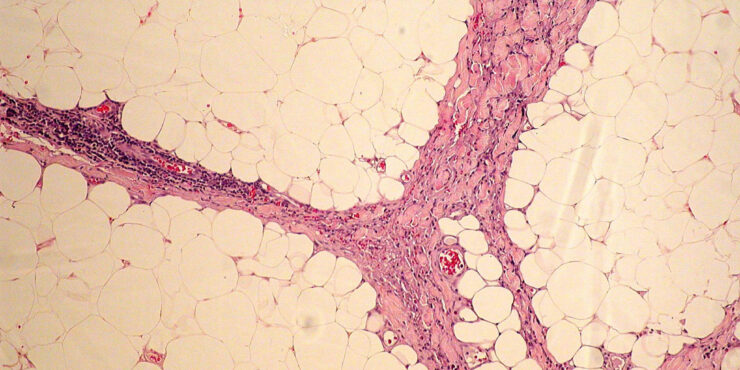

Eosinophilic fasciitis = التهاب الصفاق بالحمضات Eosinophilic Fasciitis Shulman’s Syndrome First described in 1974 , eosinophilic fasciitis is a scleroderma-like disorder characterized by inflammation and thickening of the deep fascia. It has a rapid onset associated with pain, swelling, and progressive induration of the skin leading to exaggerated deep grooving of the skin around superficial […]